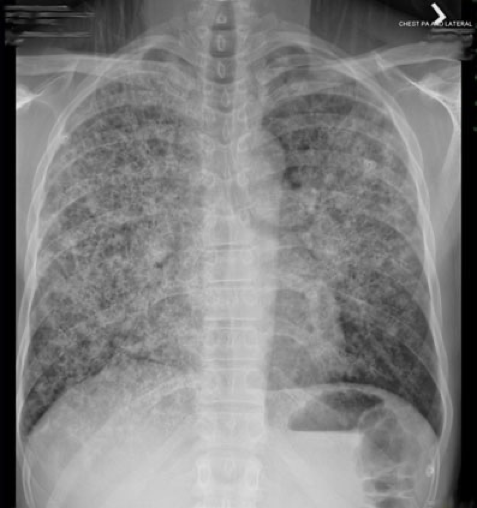

Normal CXR (PA & Lateral)

CXR showing diffuse bilateral reticulonodular interstitial infiltrates. What is the most likely diagnosis?

Cystic PJP